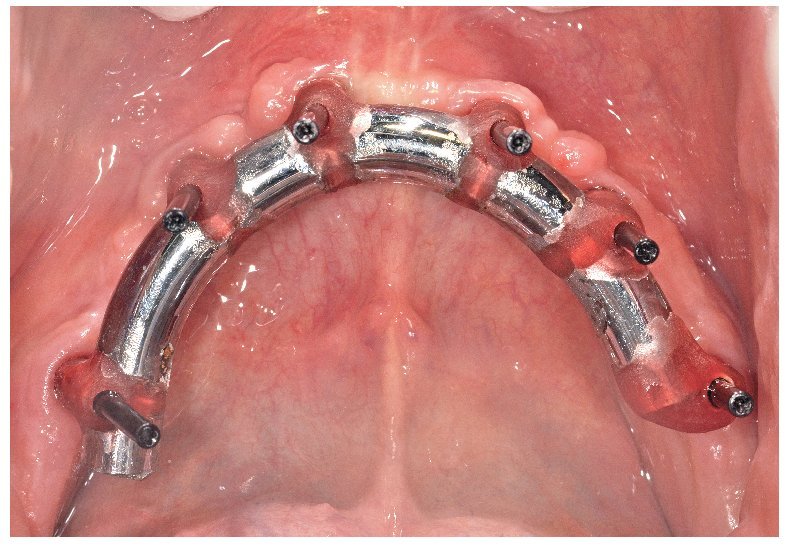

La confección de los modelos maestros requiere gran meticulosidad en el procedimiento y en la elección de materiales, dado que debe estar garantizada una fidelidad dimensional óptima. Con todo, no existe la certeza absoluta de que los modelos maestros reproduzcan adecuadamente la situación intraoral. Esto se comprueba mediante la confección de cuerpos de ensayo colados (fig. 80), los cuales se fijan sobre los pilares. Se trata de elementos de ensayo y control (figs. 81 y 82) para la introducción de la siguiente fase, durante la cual se confeccionan las estructuras fresadas. De este modo se evita el peligro de tener que repetir la confección o de puntos de soldadura tras las correcciones.

Fig. 80. Los modelos maestros de los maxilares superior e inferior con plantillas de comprobación para conciliar la posición del implante.

Fig. 81. El control clínico de la plantilla de comprobación del maxilar superior en la cavidad oral.

Fig. 82. El control clínico de la plantilla de comprobación del maxilar inferior en la cavidad oral.